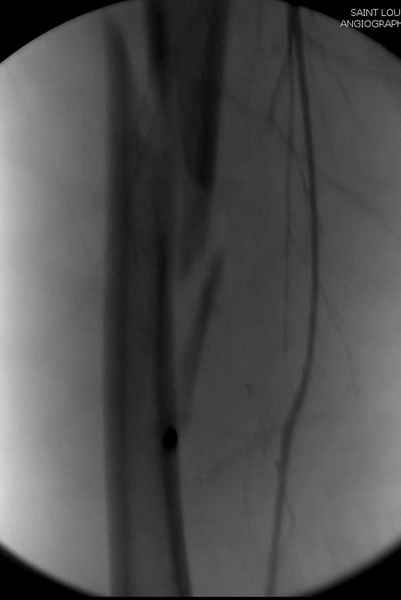

Больной долго оставался нестабильным, только на 14 день удалось заменить на антеградный интромедуллярный штифт TFN (trochanteric femoral nail) SmithNephew. После неудачной попытки закрытой репозиции, несмотря на использование "joystick", проксимальный стержень от

наружного фиксатора, (перелом начал срастаться) репозицию провели из малого доступа, затем остальные этапы операции.

Случай был представлен из-за того, что больного оперировали после наружной фиксации и был риск инфекцирования через места проведения стержней (на снимках), прошло больше 3 месяцев, выписан из амбулаторной службы из-за отсутсвия надобности дальнейшего наблюдения.